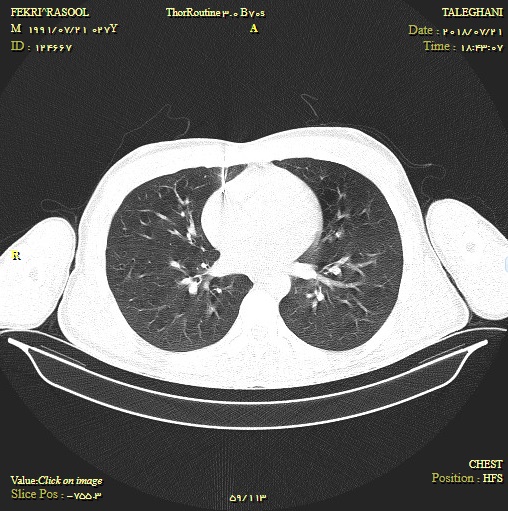

در لحظات غروب آفتاب شنبه 30 تیر ماه طلوع دوباره زندگی کارگر مشهدی به دست متخصصین بیمارستان طالقانی روشنی بخش شد. بدنبال حادثه برخورد میخ پرچ با قفسه سینه این کارگر قطعه ای از این میخ تا قلب نفوذ کرده و به لایه پریکارد رسیده و باعث تامپوناد قلبی و خونریزی دور قلب شده بود. وی بلافاصله پس از رسیدن به اورژانس بیمارستان طالقانی تحت معاینه و سپس سی تی اسکن قرار گرفت و محل جسم خارجی مشخص گردید. به دلیل خونریزی دور بافت قلب ، فعالیت آن دچار اختلال گردیده بود که بلافاصله با پریکاردیوسنتز تحت گاید سونو توسط متخصصین طب اورژانس و جراحی مقداری از خون تخلیه شد و امکان انتقال فوری بیمار فراهم گردید. عمل جراحی بیمار توسط دکتر جمعه زاده متخصص جراحی عمومی با موفقیت انجام شد و بیمار به بخش مراقبت های ویژه منتقل گردید. |